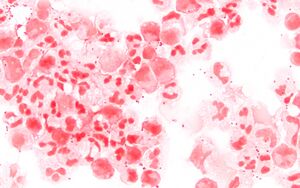

Neisseria meningitidis in cerebrospinal fluid (CSF) seen by Gram stain at 1000× magnification

يتم تشخيص مرض المكورات السحائية الغازي بشكل نموذجي بعزل النيسرية السحائية من المواقع التي تعتبر عقيمة في الحالة الطبيعية. ومع ذلك فقد تكون حساسية الزرع الجرثومي منخفضة خاصة عندما يجرى بعد بدء المعالجة بالمضادات الحيوية. إن ظهور مكورات مزدوجة سلبية الغرام في السائل الدماغي الشوكي الذي جرى تلوينه بملون غرام يقترح بقوة التهاب السحايا بالمكورات السحائية.